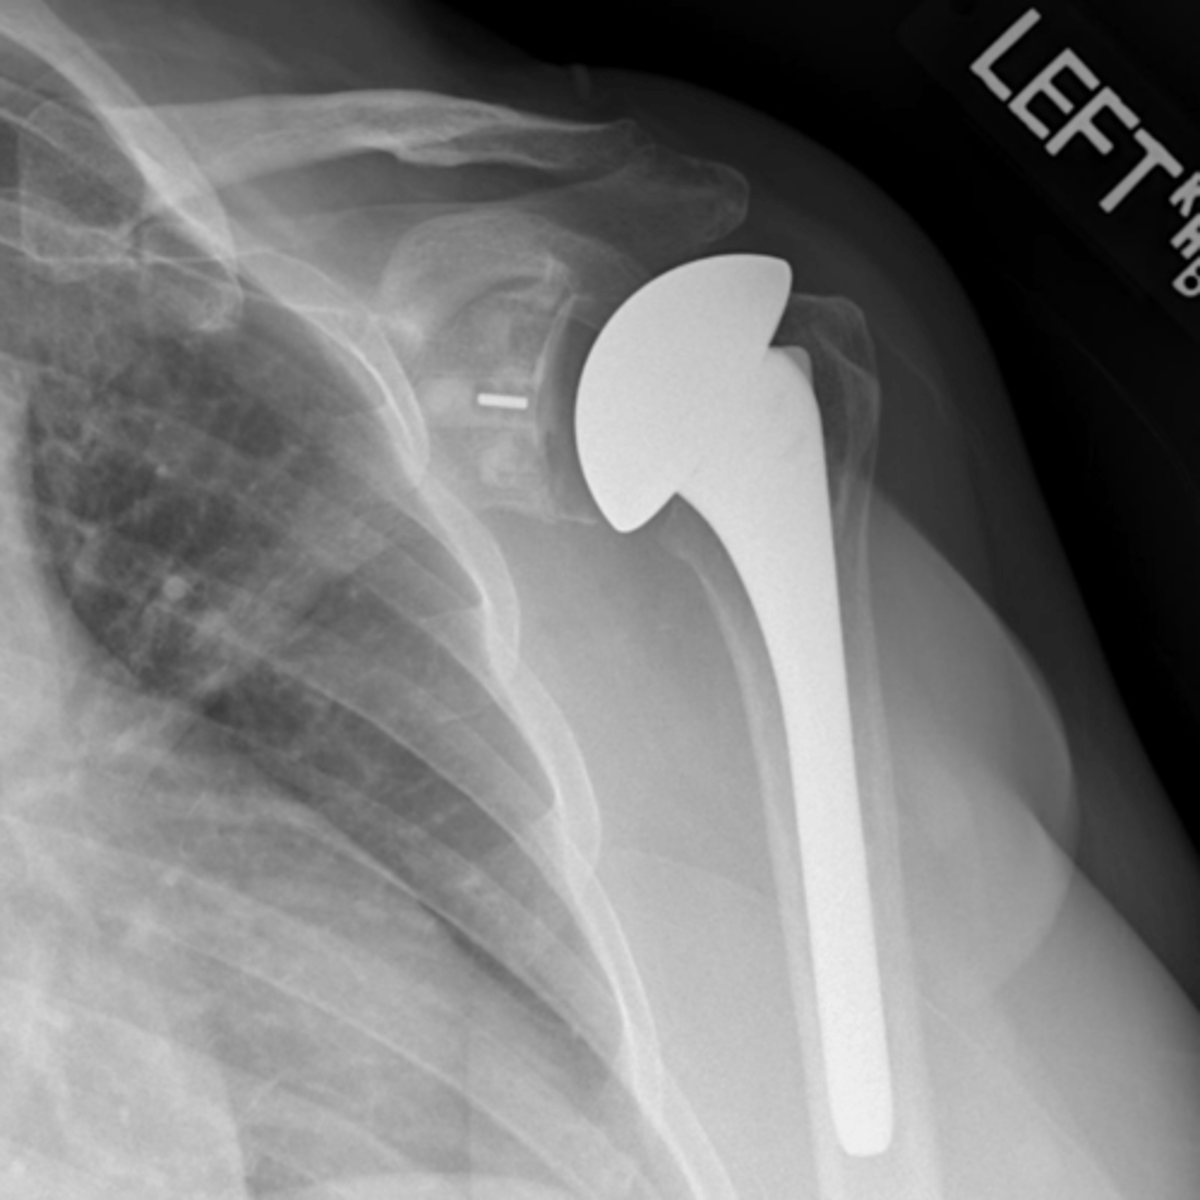

TSA

What is this image depicting?